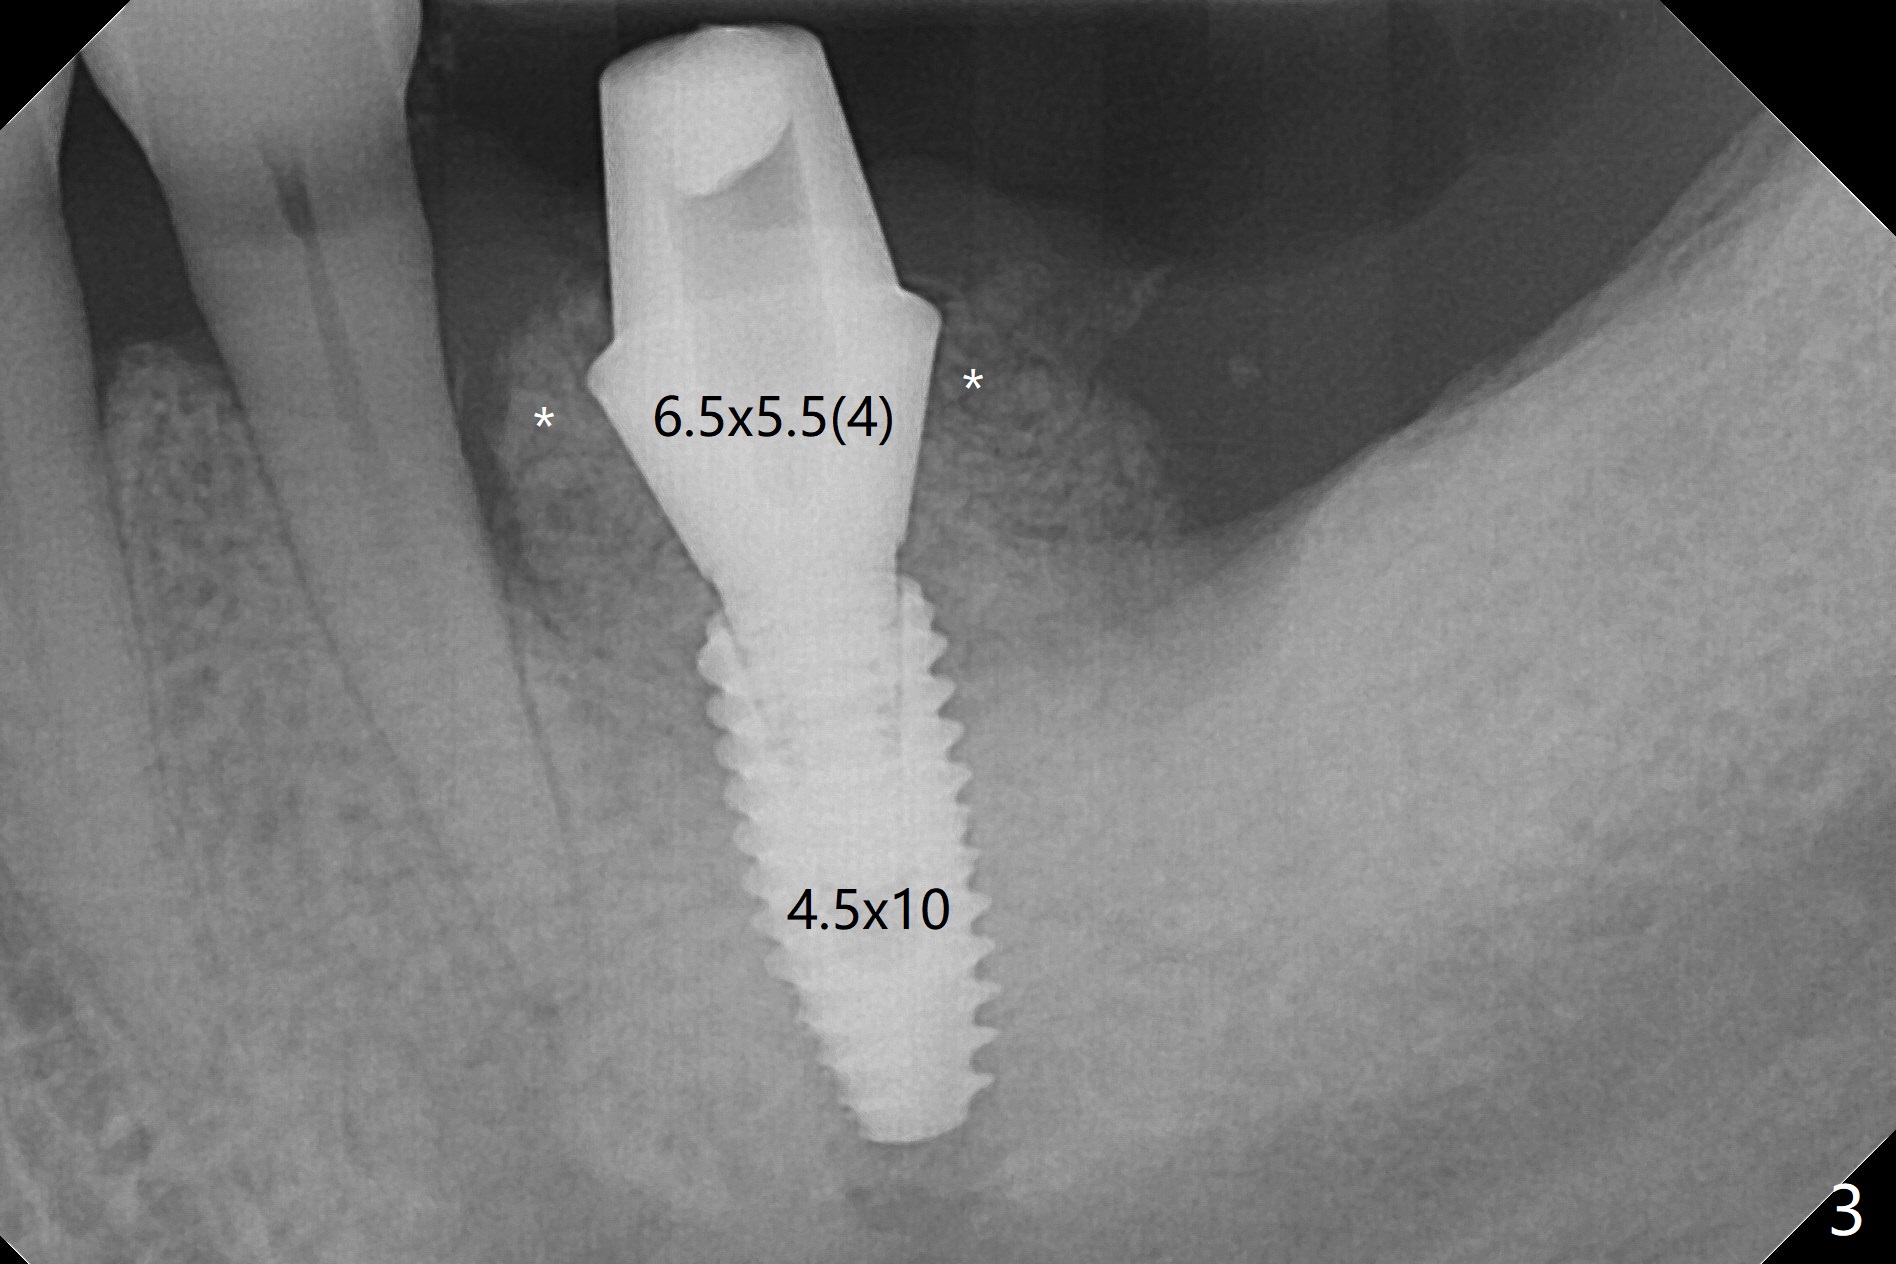

When the patient returns for #19 extraction (Fig.1), there is no 5x10 mm implant available. In fact the smaller one (4.5x10 mm) is able to achieve insertion torque >60 Ncm with more room for autogenous bone/allograft horizontally (Fig.2 *). After insertion of a definitive abutment (6.5x5.5(4) mm), more allograft is placed coronally (Fig.3 *). The gingiva that was between the mesial and distal roots before extraction (Fig.1 *) is transferred distal (Fig.4.5 *). An immediate provisional (Fig.6 P) is fabricated to close the socket opening, followed by periodontal dressing (data not shown). The latter is partially detached 2 weeks postop (Fig.7 D). When it is removed, some of possibly collagen plug is exposed distobuccally (Fig.8). When the plug is removed, some of the bone graft (Fig.9 *) is exposed distal to the provisional (P). New periodontal dressing is applied to keep the exposed graft in place. There is no apparent thread exposure 4 months postop (Fig.10). The abutment is loose 4 months post cementation, probably related to unfavorable crown/implant ratio; but when the abutment is retightened, there is a gap between it and the implant (Fig. 11 >). After relieving the proximal contact of the crown, the abutment is retightened one more time with the same gap (Fig.12 >). In fact the latter is present previously. A narrower abutment with longer cuff appears to be completely seated, probably avoiding contact with the regenerated crestal bone (Fig.13 *). If the new crown gets loose, bury a driver inside the abutment.